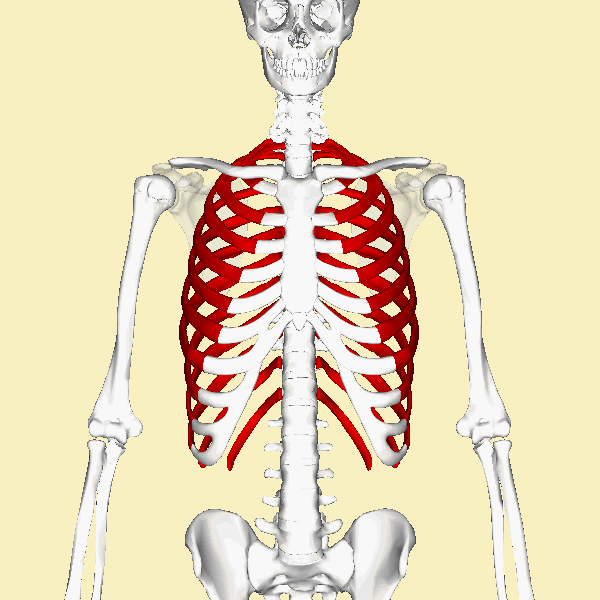

Identification of Axial Bones